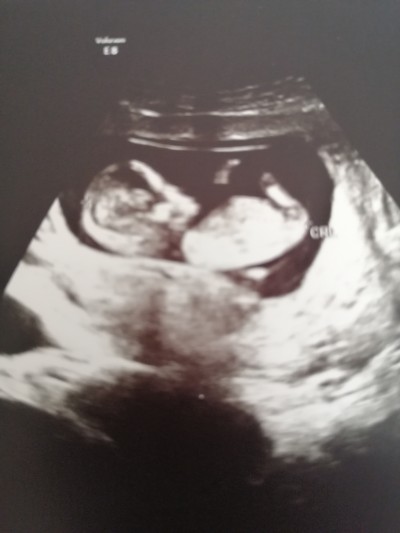

kızlar doktorum 12. Haftada büyük ihtimalle kız dedi bacak arasında bir şey göremedim dedi aniden baktı ben anlamadm zaten değişen oluyor mu bu haftadan sonra

banada 12de kiza benziyor dedi 16 da net kiz oldugunu ogreendim nub'a gore yorumlamisti cikinti asagiya bakiyordu yukari bakinca erkek oluyormuş

Benim hemen ultrason bacak arasından geçirdi bir şey görünmüyor dedi canım detaylı o bölgeye bakmadı büyük ihtimal kız dedi

Kesinleşme haftası 15 yila 16. Haftalarda net belli oluyor

Erkek olsa 12. Haftada orası çıkıntı olmaz mıydı

Benimki cinsiyeti erkek 16. haftada belli oldu hagi doktora gidersen git cinsiyeti 15 ila 16. Haftada belli olur seninki daha küçükmüş masAllah oyuzden gozukmemesi normal

Bacak arası boş kız dedi canım sonradan erkeğe döner mi. Döner mi dediğim erkek der mi